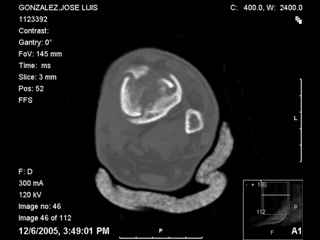

A 56 year old laborer fell off a wall approximately 5 months ago. He sustained an open pilon fracture. He was treated with debridement and external fixation. After he was treated for 4 months, the external fixator was removed.

I have attached his x-rays. I have also attached an WMV movie file of his axial CT (if you are unable to view this, I can post an MPEG file).

It seems to be a definite nonunion from the plain XRs.

The subtalar joint looks okay from what we can see on the lateral x-ray so I wouldn't want to damage it if it can be avoided. If thorough workup (WBC, ESR, CRP) shows no evidence for infection, he's a nonsmoker (or has quit) and there's no sign of infection at surgery, I would try a "moderately invasive" ORIF with debridement and autologous bone grafting. I think with a precontoured plate with locking screw capability one could get adequate fixation distally to allow immediate ROM and provide compression across the fracture.